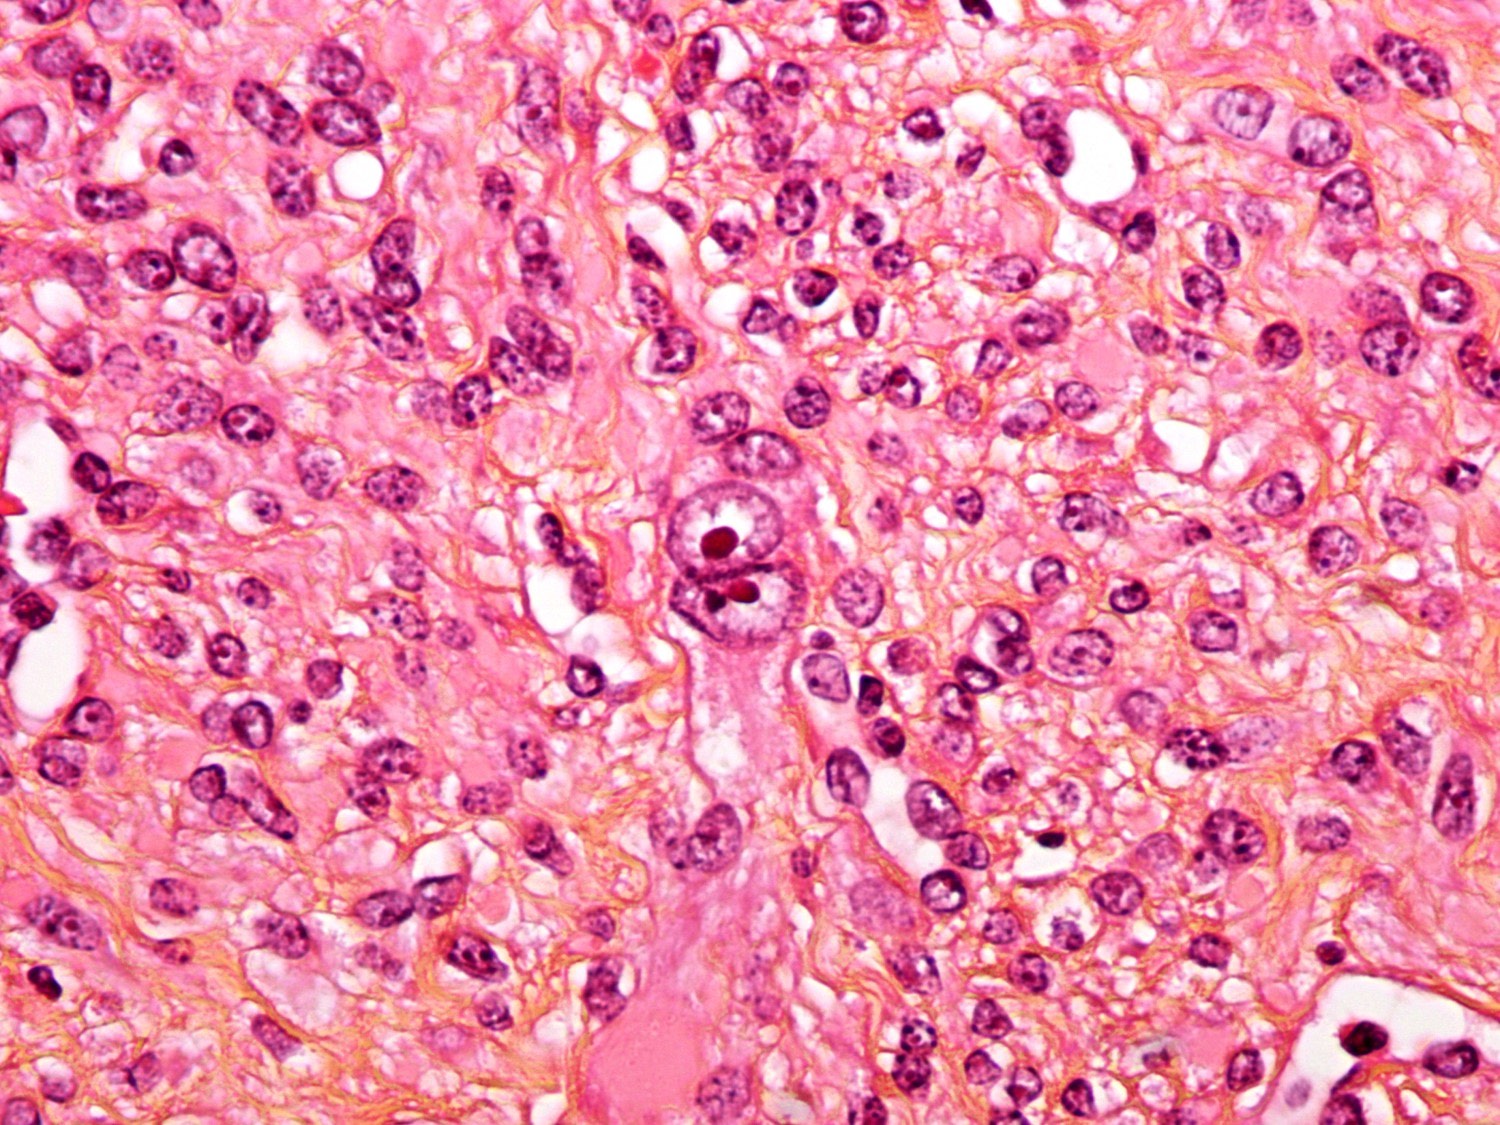

uterus leiomyoma atypical bizarre webpathology pathology tumor comments

leiomyoma uterus deficient fh epithelioid pathologyoutlines